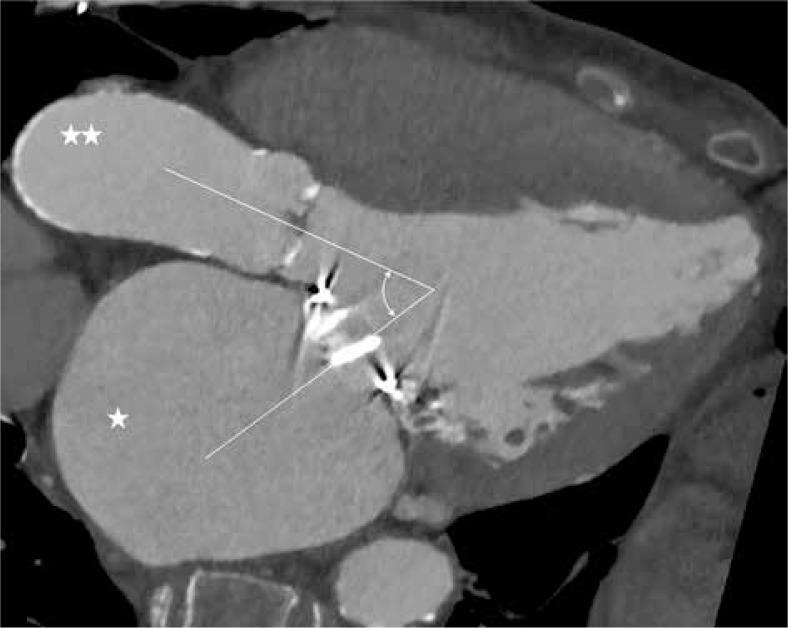

TAVI in patients after MVR is feasible. Meticulous preinterventional echocardiographic and computed tomography planning is essential. Although recommended in previous reports, TEE guidance may not necessarily be obligatory during the procedure.

回顾性评估有MVR病史且接受TAVI患者的临床特征、详细的超声心动图和计算机断层扫描测量结果、手术及住院结局,以及根据VARC-2标准在随访时的任何瓣膜干预或主要不良心血管事件。

结论

MVR术后患者进行TAVI是可行的。细致的介入前超声心动图和计算机断层扫描规划至关重要。尽管既往报告中推荐,但术中不一定必须采用经食管超声心动图(TEE)引导。